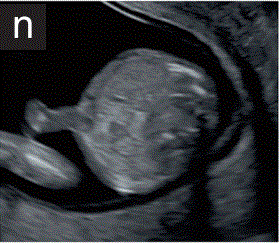

7.2 腹壁

7.2.1 12周后应记录脐带的正常插入情况(图2n)。生理性中肠疝出现长达11周,应与脐膨出和腹裂区分。

胎儿mt是什么检查什么疼吗【文献学习/规范指南】ISUOG实践指南(2023更新): 11-14周胎儿超声检查(全文)_https://www.jmylbn.com_新闻资讯_第24张

图2 11+0至14+0周时,可作为详细胎儿超声检查的一部分获得的解剖图。

(n)胎儿腹部横断切面,显示完整的前腹壁和脐带插入部位。